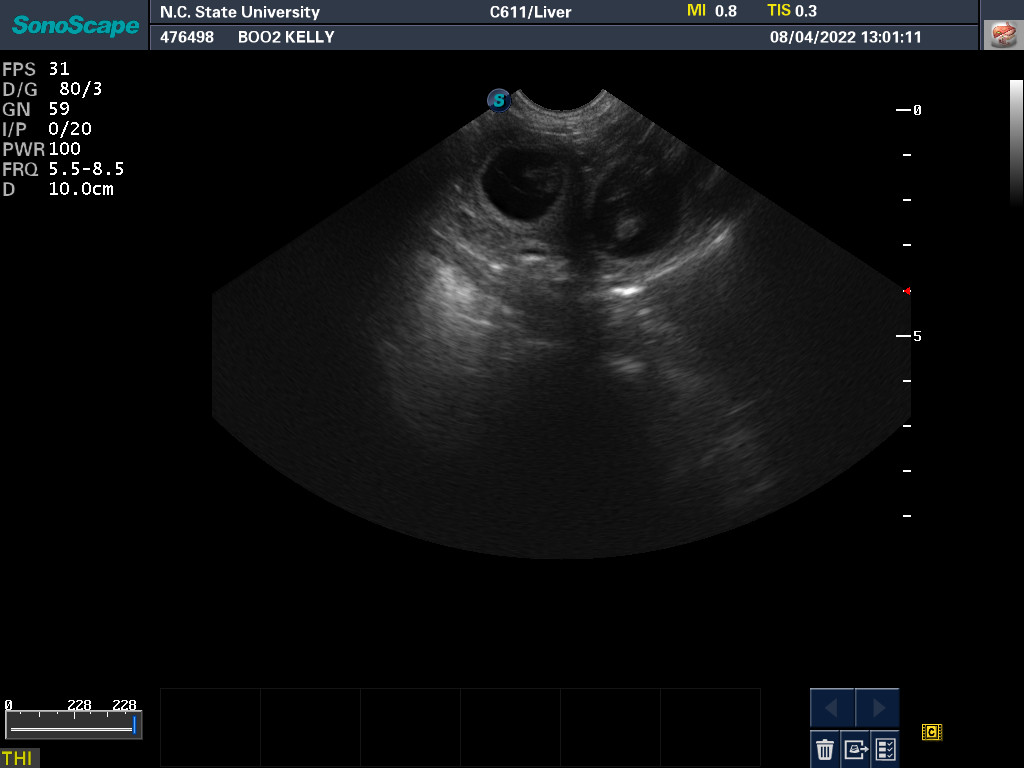

4 Aug 2022

Ultrasound today by the theriogenology (reproduction) veterinarians at NC State University showed that Boo is pregnant with two, possibly three puppies. It is difficult to accurately count puppies using ultrasound.

If all goes well, puppies are due around 5 September.

My repro vets also checked Boo's puppies by ultrasound, counting the puppy heart rates and looking for movement in the puppy GI tracts. All looks good!